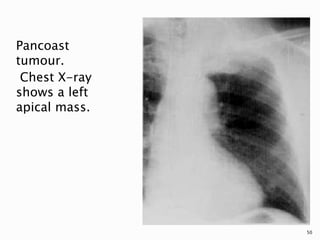

Pancoast

tumour.

Chest X-ray

shows a left

apical mass.

50

 Findings suggestive of malignancy include

an apical cap >5 mm, asymmetry of apical

caps >5 mm, an apical mass, and adjacent

bone destruction.

 Clinical symptoms of arm pain and a

Horner's syndrome are classically

associated with a Pancoast tumor.

49